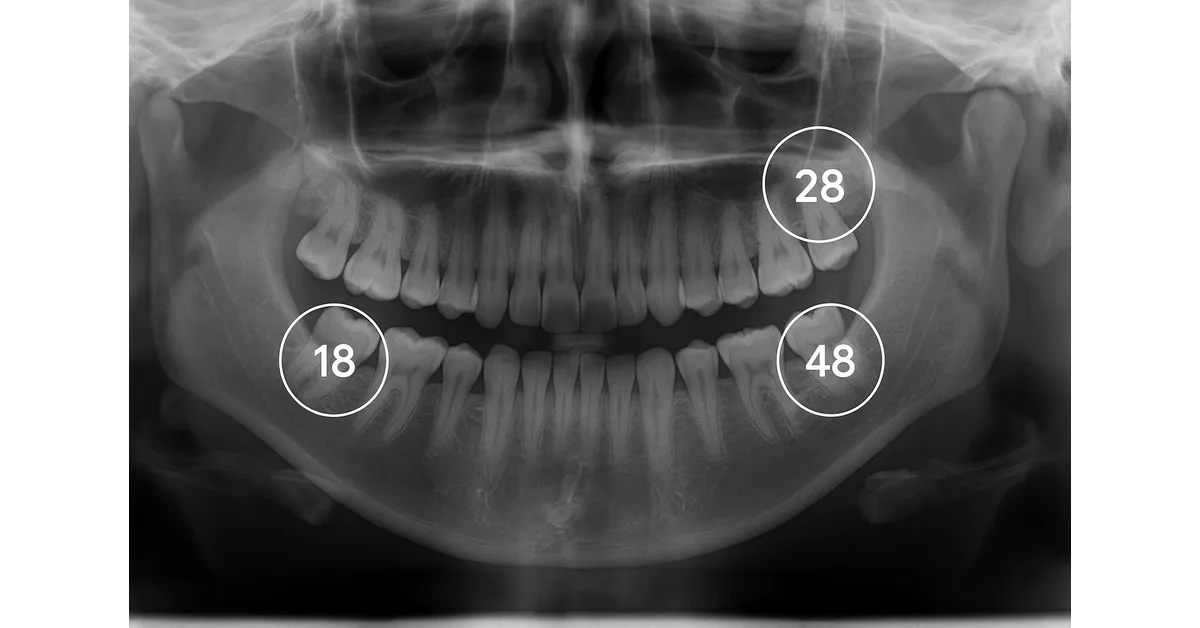

شمارهگذاری مولر سوم در فک بالا و پایین با نمای واقعی

دندان عقل شماره چند است در سیستم FDI (دو رقمی)

در سیستم جهانی FDI دهان به چهار ربع تقسیم میشود؛ فک بالا سمت راست (۱۰۰)، فک بالا سمت چپ (۲۰۰)، فک پایین سمت چپ (۳۰۰) و فک پایین سمت راست (۴۰۰). در هر ربع، شمارهگذاری دندانها از وسط دهان شروع میشود و تا انتها ادامه دارد. بر این اساس:

دندان عقل بالا راست شماره ۱۸ است.

دندان عقل بالا چپ شماره ۲۸ است.

دندان عقل پایین چپ شماره ۳۸ است.

دندان عقل پایین راست شماره ۴۸ است.

بنابراین وقتی میپرسیم دندان عقل شماره چند است، در سیستم FDI پاسخ روشن و دقیق این است که دندانهای عقل با اعداد ۱۸، ۲۸، ۳۸ و ۴۸ مشخص میشوند.

دانستن این شمارهها باعث میشود بیمار هنگام مشاهده عکس OPG یا شنیدن نظر دندانپزشک درباره مشکلاتی مثل نهفتگی، التهاب لثه یا فشار به دندانهای کناری، دقیقاً متوجه شود کدام دندان مورد نظر است.

در نتیجه آگاهی از این شمارهگذاری کمک میکند هم بیمار پاسخ پرسش «دندان عقل شماره چند است» را بداند و هم با آرامش بیشتری روند درمان خود را دنبال کند.